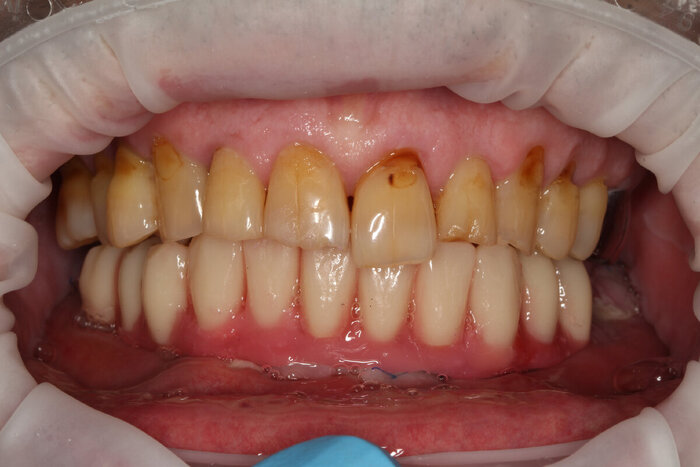

Делаем фото до:

И во рту:

До.

До имплантации.